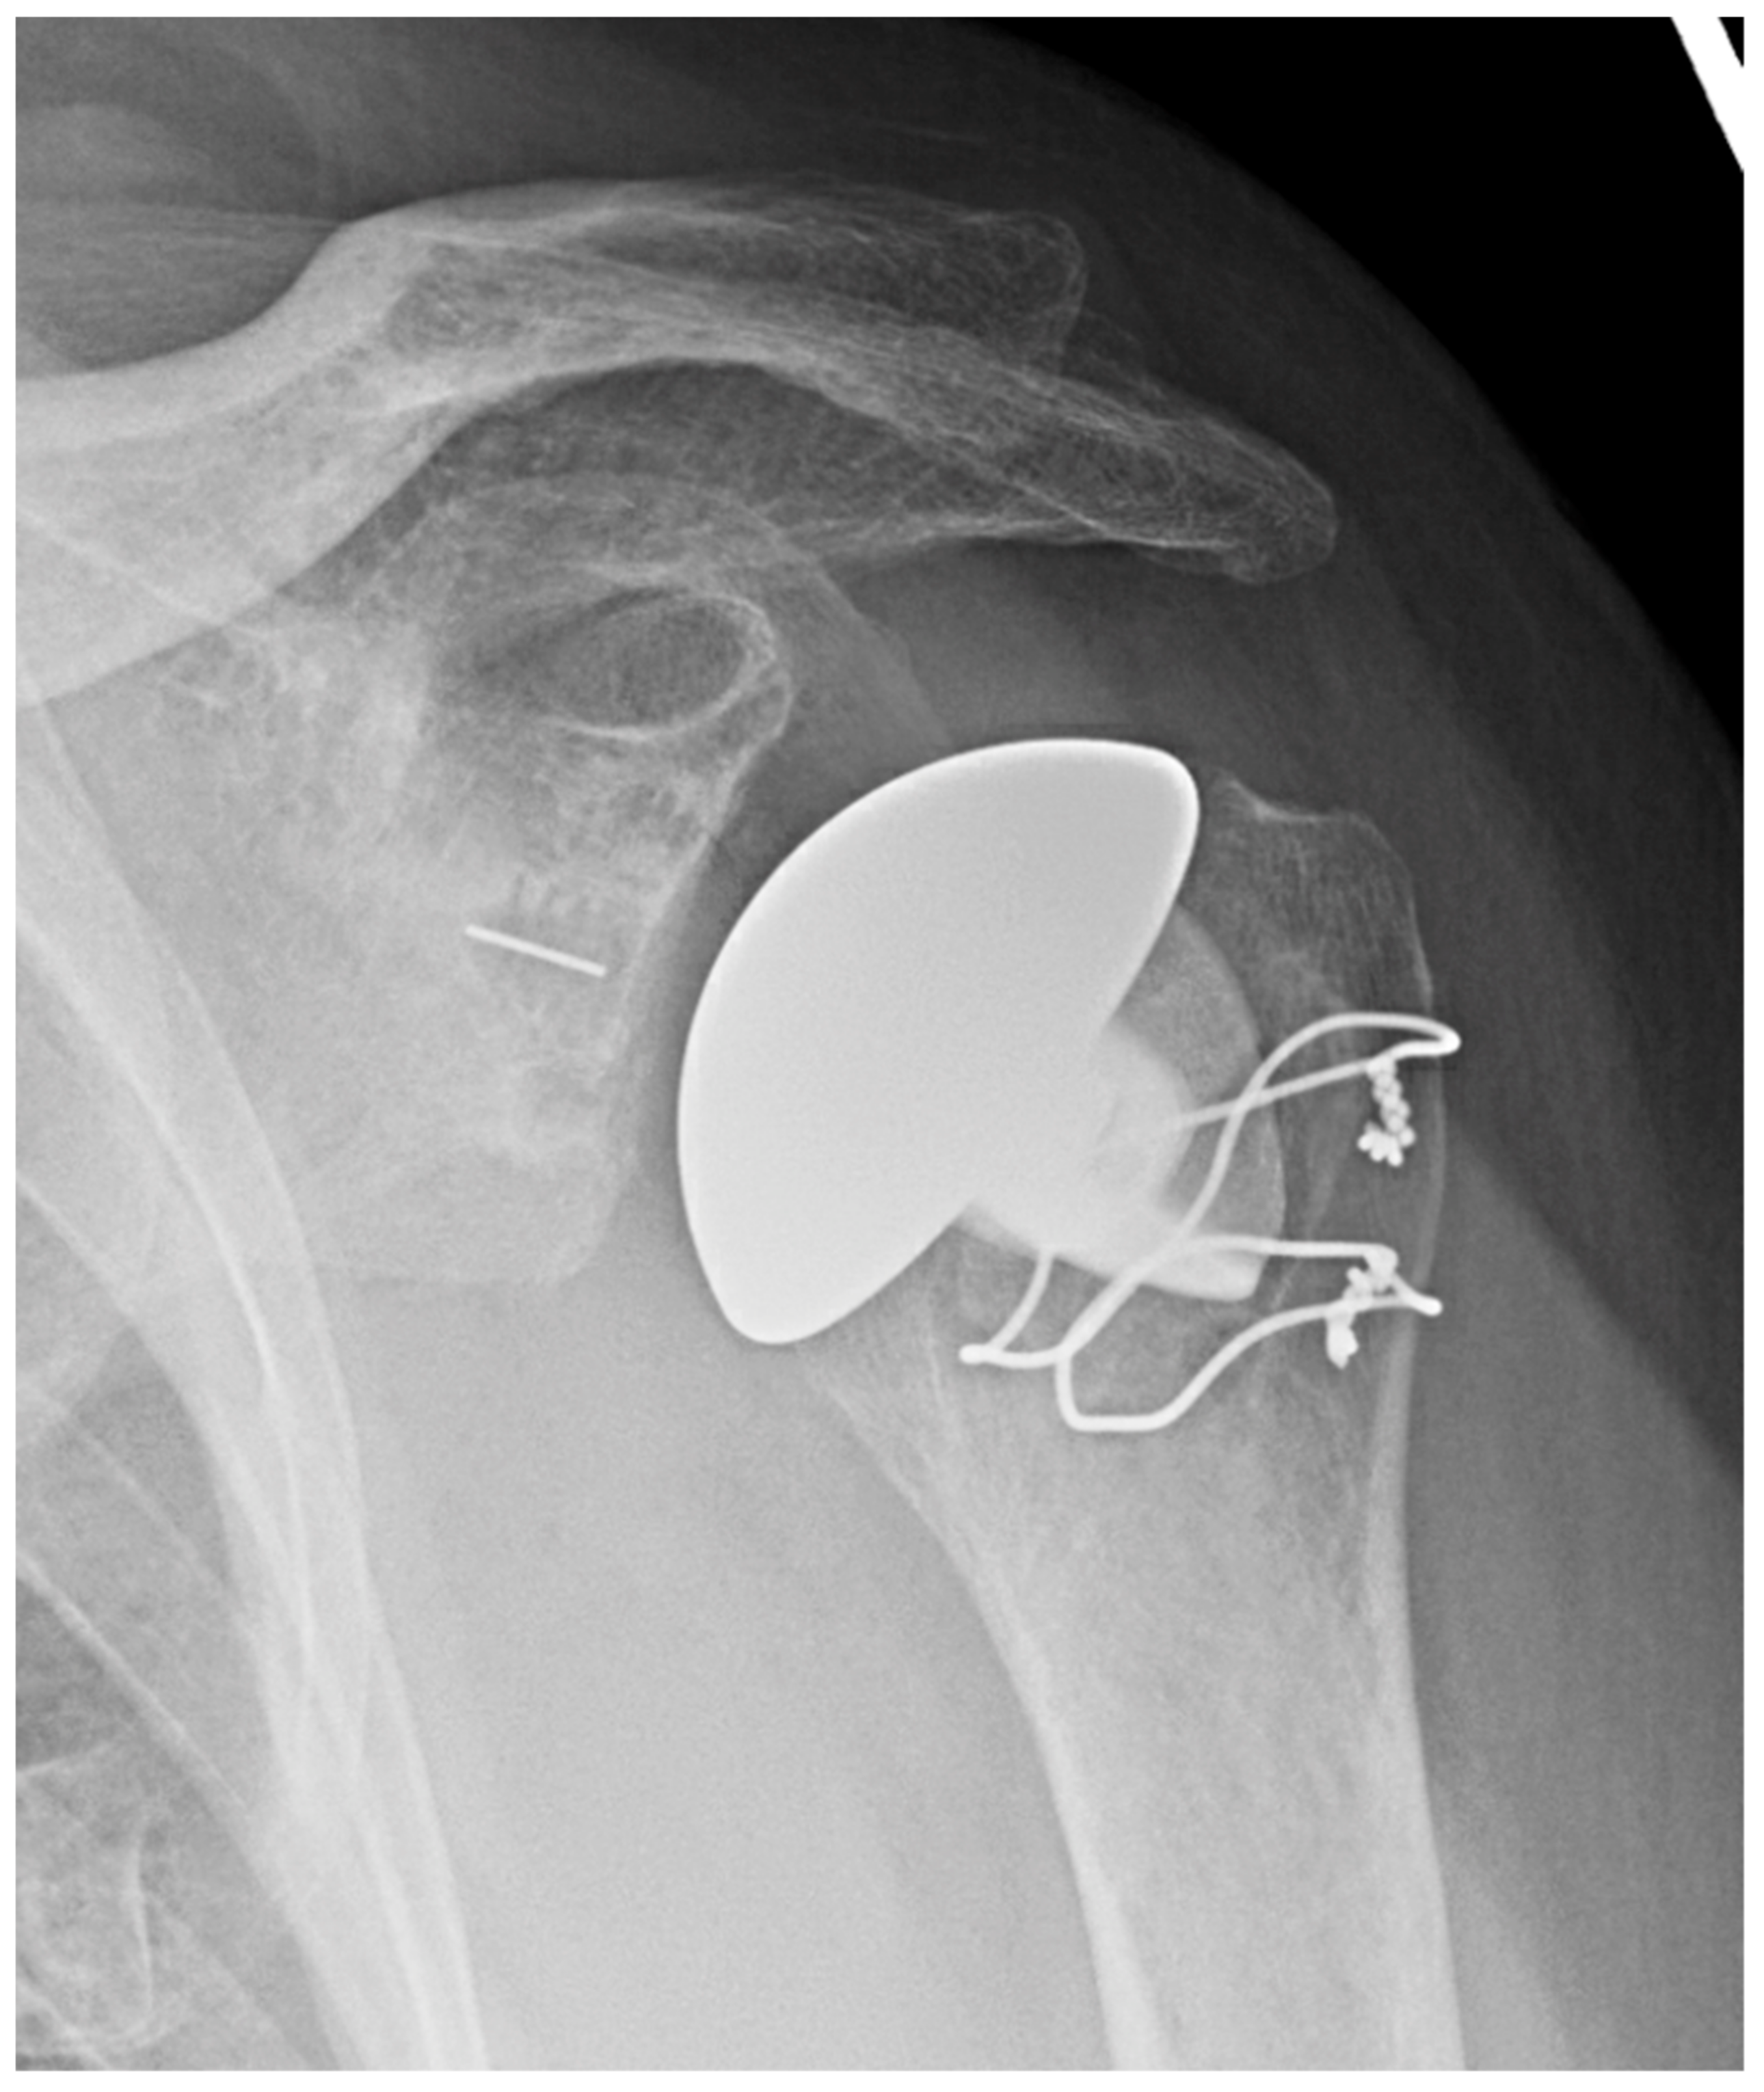

2.1.1. Stemless Implants

3.2.2. Inlay vs. Onlay Implants